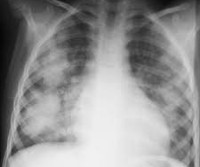

• Рентгенологические исследования. Рентгенография органов грудной клетки выявляет усиление выраженности легочного рисунка, наличие инфильтратов в виде облаковидных теней.